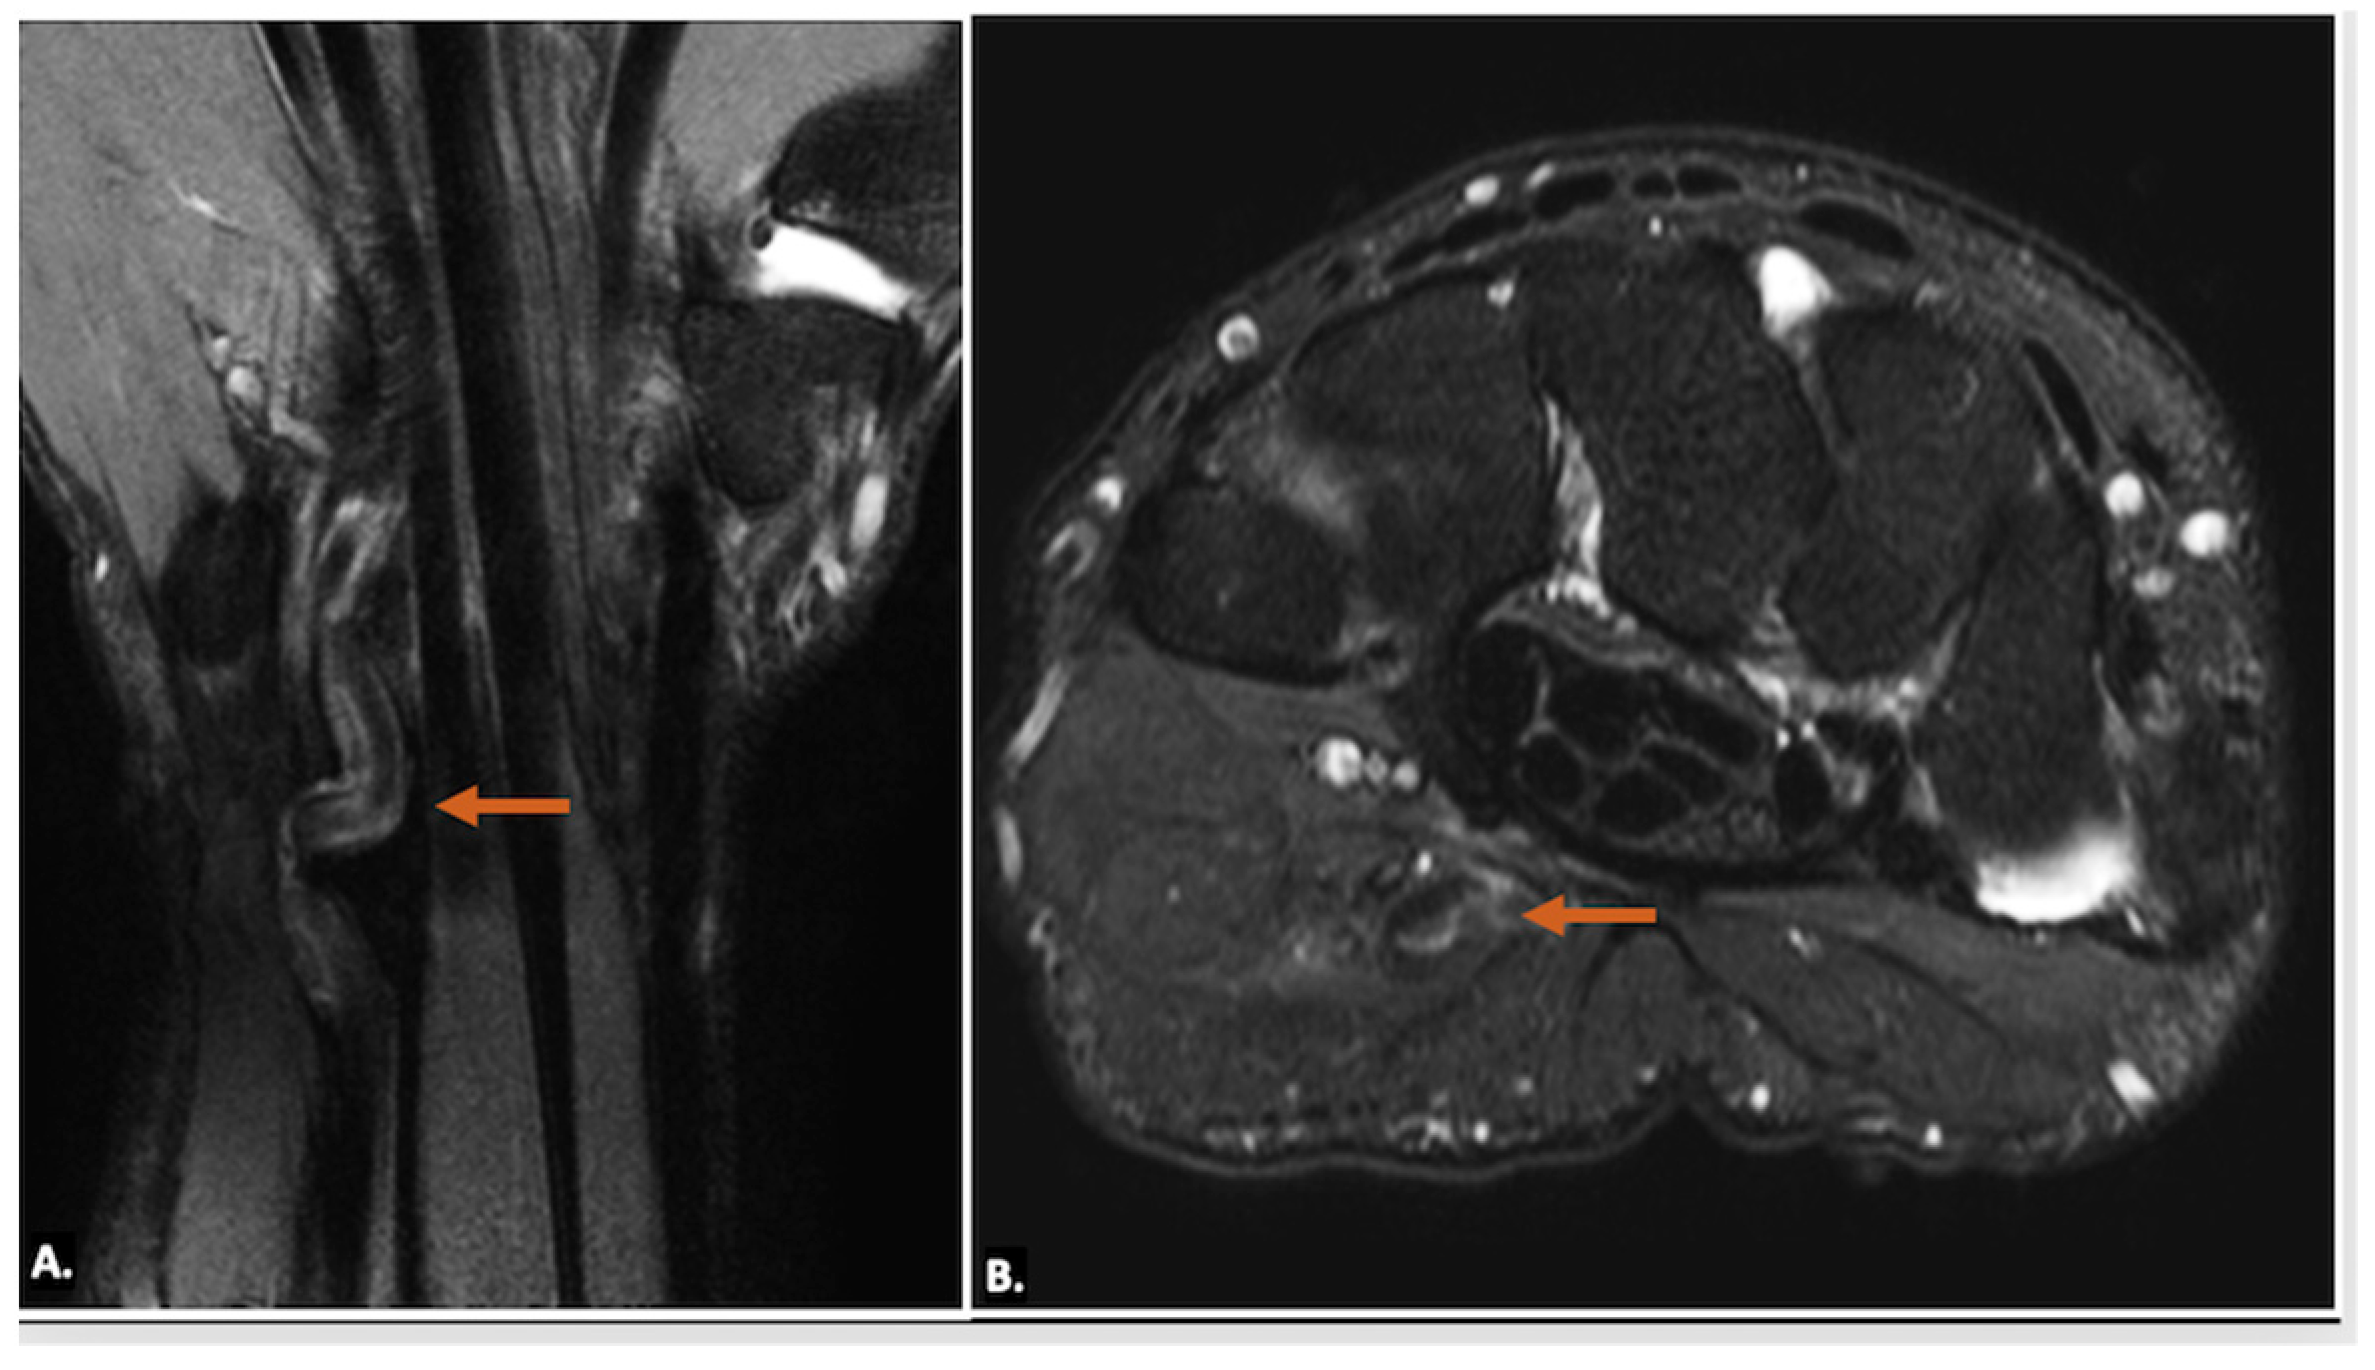

On MRI, ganglion cysts are well defined, hypointense on T1-weighted images, and hyperintense on T2-weighted images, reflecting their fluid content. Post-contrast images may show thin peripheral enhancement, but the cyst itself does not enhance. Unlike more complex cystic lesions, ganglion cysts usually do not contain calcific foci or haemorrhage. The cyst can cause displacement or compression of the ulnar nerve, which may show an increased signal on T2-weighted images, indicating oedema (Figure 7) [15].

Figure 7.

MRI reveals a well-defined, fluid-filled lesion within Guyon’s canal, consistent with a ganglion cyst (orange arrow), causing compression of the ulnar nerve (UN) (yellow arrow). Image (A) shows an axial view, while image (B) presents a long-axis view.